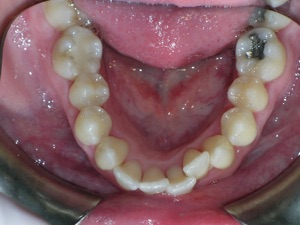

Now for the final results.

Needless to say, we were both quite happy with the outcome. Using elastics we were able to push back the back teeth and create space for the two teeth stuck behind.

Hope you like it too!